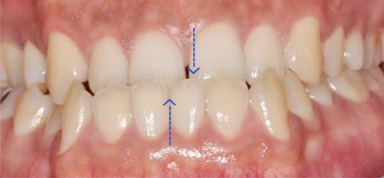

주걱턱으로 앞니가 서로 거꾸로 물리고 어금니가 제대로 물리지 않는 남환, 타 병원에서 양악 수술 진단을 받고 내원하셨습니다.

고운미소에서 교정용 미니스크류를 이용하여 아래 치열은 후방이동, 위 치열은 전방으로 이동하는 치료를 진행하였습니다.

비 수술교정치료 이후 제대로 물리지 않던 어금니와 앞니 배열이 정상적으로 돌아왔습니다.